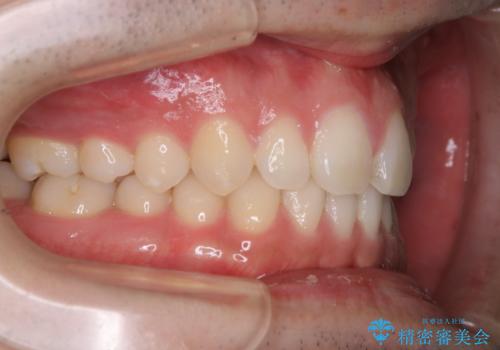

親知らずを抜いて1週間後にPMTC 歯のクリーニング

- 親知らずの抜歯後の約1週間後に抜糸(縫った部分の糸とり)で来院されました。その際、抜歯後は傷口が怖くて歯磨きが上手くできず、汚れや口臭が気になるためクリーニングも希望されました。

抜歯後は多少出血したり、違和感や痛みを感じたりすることがあります。そのため親知らずを抜いたり、外科的な処置をするといつも通りの歯磨きがしづらくなります。また、傷口の周りが心配で、歯ブラシをするのが怖くなるものです。抜歯後落ち着いたら、歯科医院にて専門の機械を使用しクリーニングをすることがおすすめです。抜歯前や後にPMTCを行うことで、お口の中の健康維持につながり、その後の感染・腫れ・口臭予防などになります。

親知らず抜歯後正常に治癒が進んでいれば1週間後から可能です。